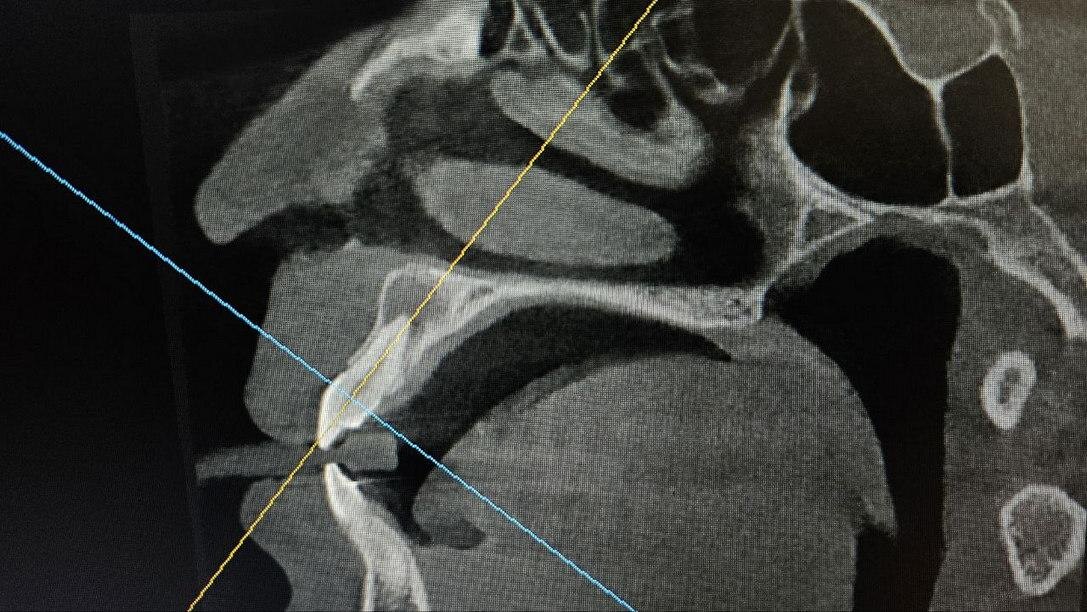

Хорошо, когда зубы не болят, но только не в случае Эльвиры. Если бы зуб 1.1 начал болеть, расшатываться или давать какой-то дискомфорт, девушка обратилась бы за лечением раньше. Но пульпа умерла незаметно для пациентки, в результате чего начала расти киста. К моменту обращения к врачу, киста распространилась на апекс соседнего зуба 1.2 и практически проросла в пазуху носа.

Киста зуба 1.1, которая уже распространилась на апекс зуба 1.2